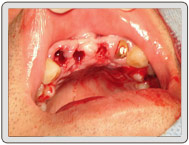

50年次,缺上顎正門牙二顆,右側門牙(殘根)一顆。

計畫:植入共三顆,右上側門牙採即拔即種,立即植牙。利用超音波骨刀立即拔牙並使用3D雷射微創植牙術,不開刀、不翻瓣術後無腫無痛情況良好,並作臨時牙冠維持美觀。

治療中

植入植體